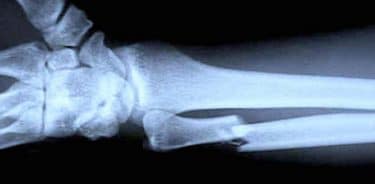

Kemik kırığı teşhis sürecinde öncelikle doktor fizik muayene yapar, belirtileri tespit eder ve teşhis koyar. Hasta ile – ya da hasta uygun şekilde iletişim kuramazsa – arkadaşlar, akrabalar ya da tanıklar ile yaralanmaya neden olan durumlar hakkında görüşür. Sonraki aşamada genellikle röntgen çekilmesi gerekir. Röntgen, iç dokuların, kemiklerin ve organların bir resmini verir. Kırıkların çoğu bir röntgen tarafından teşhis edilir. Bazen röntgende kırık görülemeyebilir. Bu özellikle bazı bilek kırıkları, kalça kırıkları (özellikle yaşlı insanlarda) ve stres kırıklarında sık görülen bir durumdur. Bu gibi durumlarda doktorunuz bilgisayarlı tomografi (BT) taraması, manyetik rezonans görüntüleme (MRI) veya kemik taraması gibi testler yapılmasını gerekli görebilir.

Kemik kırığı teşhisi ve röntgen filmi